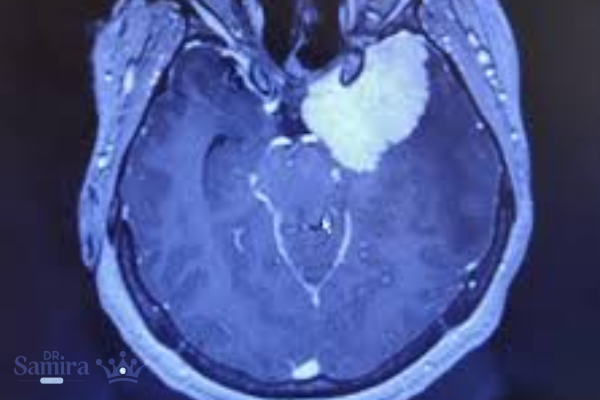

روشهای تشخیص و بررسی تصویربرداری

برای تشخیص دقیق این تومور، تصویربرداری نقش اساسی دارد. MRI با تزریق ماده حاجب، ابزار انتخابی پزشکان است. در MRI تودهای با حدود مشخص و جذب بالای گادولینیوم مشاهده میشود که در داخل یا اطراف سینوس کاورنوس قرار دارد. شکل تومور ممکن است نامنظم باشد و گاهی بخشی از دیواره شریان کاروتید را درگیر کند. CT Scan نیز در مواردی که لازم باشد وضعیت استخوانهای قاعده جمجمه بررسی شود، بهکار میرود؛ زیرا مننژیومها غالباً باعث کلسیفیکاسیون یا تغییرات استخوانی خفیف میشوند.